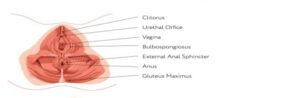

SUELO PÉLVICO

En el estrecho medio de la pelvis se insertan los músculos profundos del suelo pélvico. Por su disposición transversal y opuesta al diafragma torácico, también se lo denomina diafragma pélvico.